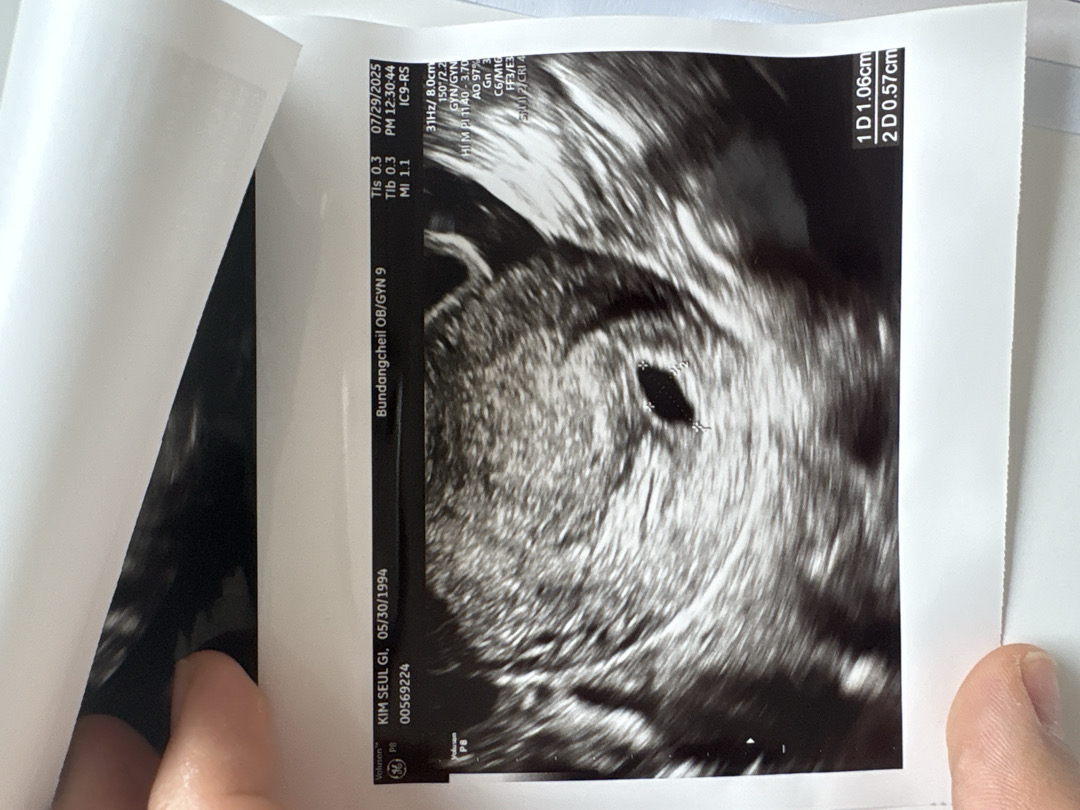

마지막 생리시작일이 5월 20일이고 평소 주기도 60~70일 정도 되어요 ㅠㅠ 병원에선 몸에 아무 문제없고 그냥 생리주기가 긴 여성이라고 하더라고요! 다행이긴한데 주기가 길어서 주수도 정확하지 않은 상태에요 병원에서는 아기집보고 초음파기준 5주 6일차라고 하셨는데 아직 난황이 안보여서 걱정이에요 ㅠㅠ 주기가 길어서 착상이 늦게된거면 좋겠네요..